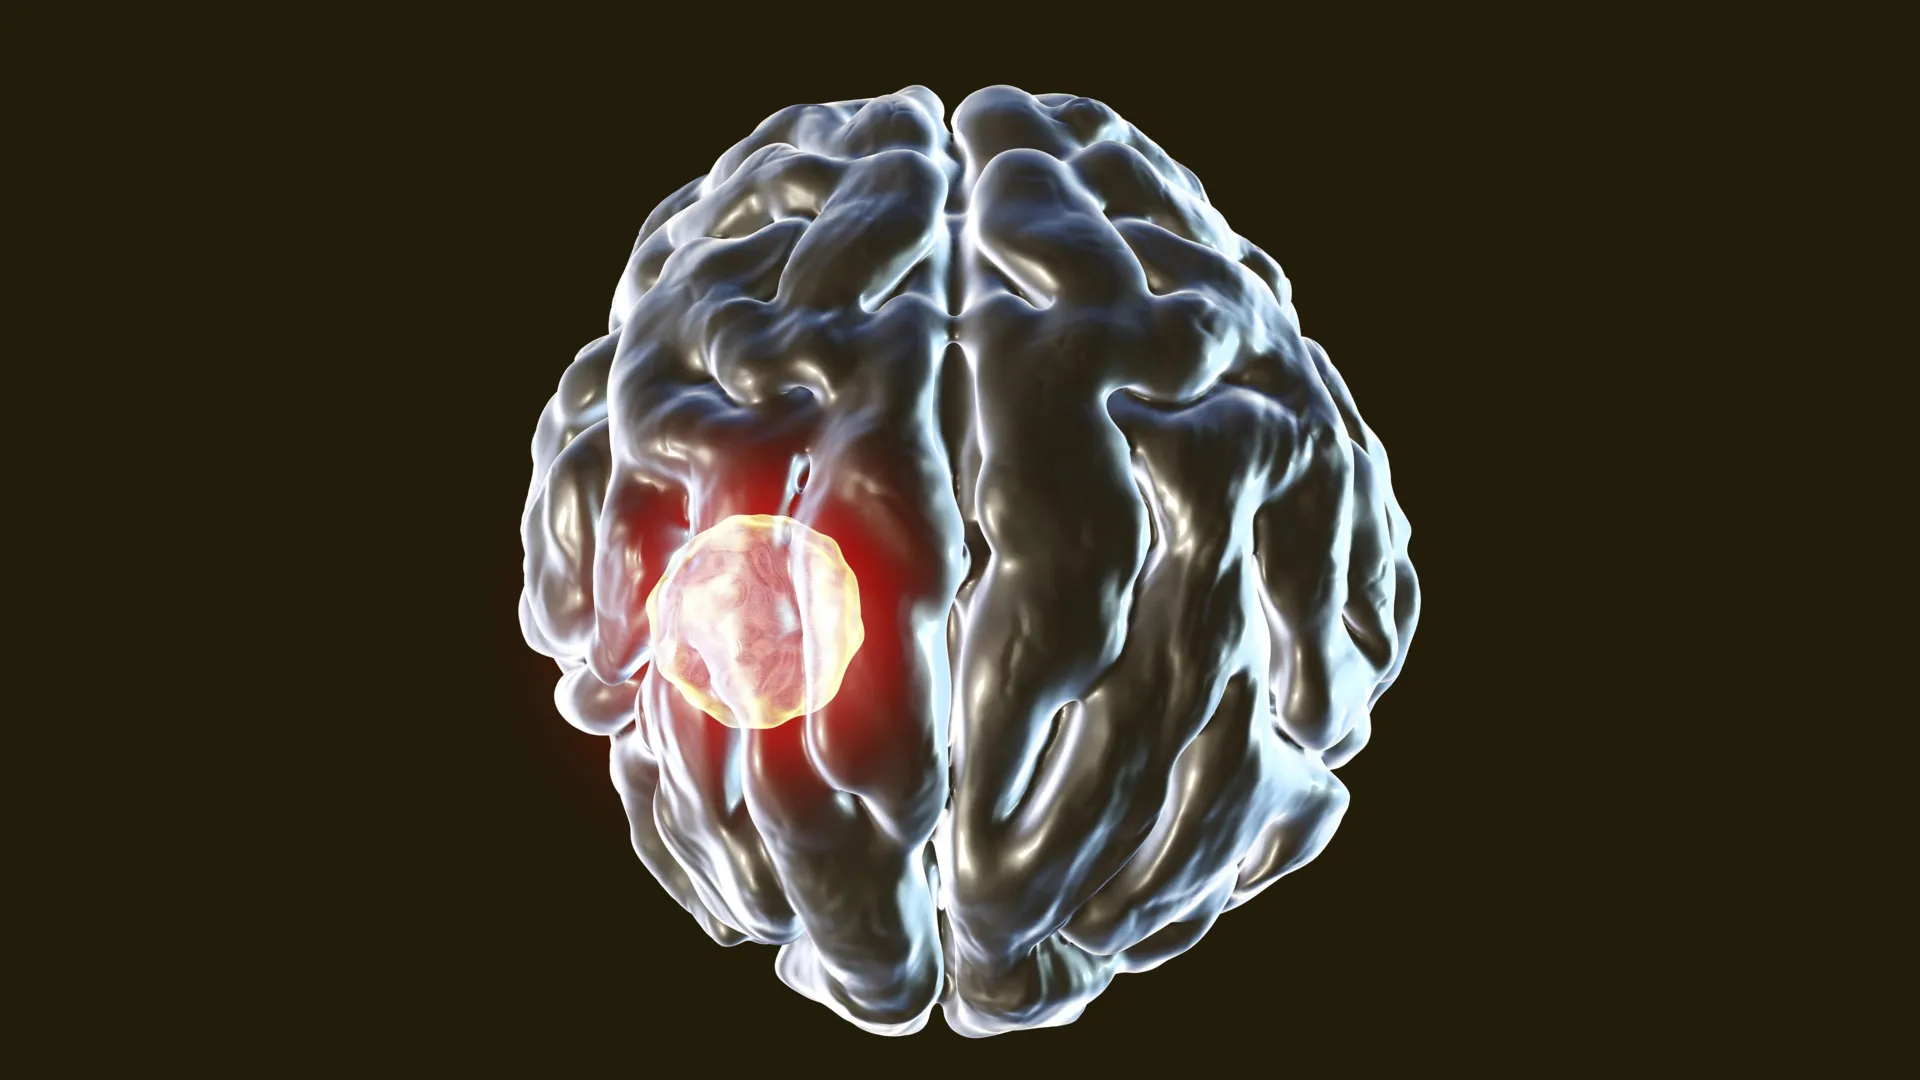

The Toxoplasma gondii parasite represents a significant global health concern, capable of affecting a broad spectrum of warm-blooded creatures. Human exposure most commonly occurs through indirect pathways, such as direct contact with domestic felines, consumption of produce contaminated with parasite oocysts, or ingestion of inadequately cooked meats. Once it breaches the body’s defenses, the parasite embarks on a journey, disseminating to various organs before ultimately establishing a chronic presence within the brain, where it can persist indefinitely. Epidemiological estimates suggest that approximately one-third of the world’s population harbors Toxoplasma gondii. Intriguingly, the vast majority of these infected individuals remain asymptomatic. However, when symptoms do manifest, a condition termed toxoplasmosis, the illness poses the most severe risks to individuals whose immune systems are already compromised, such as those undergoing chemotherapy, organ transplant recipients, or individuals with HIV/AIDS.

The observable differences in health outcomes between the two groups were stark and highly informative. Mice equipped with functional caspase-8 in their T cells remained remarkably healthy, demonstrating effective control of the infection. In stark contrast, mice lacking this enzymatic defense mechanism succumbed to severe illness, ultimately proving fatal. Post-mortem examinations of brain tissue from these affected mice revealed a significantly elevated prevalence of CD8+ T cells that had been successfully invaded and infected by the Toxoplasma parasite.